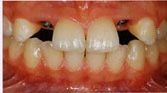

El primer paso es la instalación de los implantes

dentarios en el maxilar.

El segundo

paso, luego de una espera de 3 a 4 meses,

se colocan unos intermediarios a través de la encía, que son los que sostendrán

la futura prótesis.

El tercer y último paso es la colocación del sistema

protésico elegido, sobre los intermediarios colocados en el segundo paso, en

forma firme y precisa.